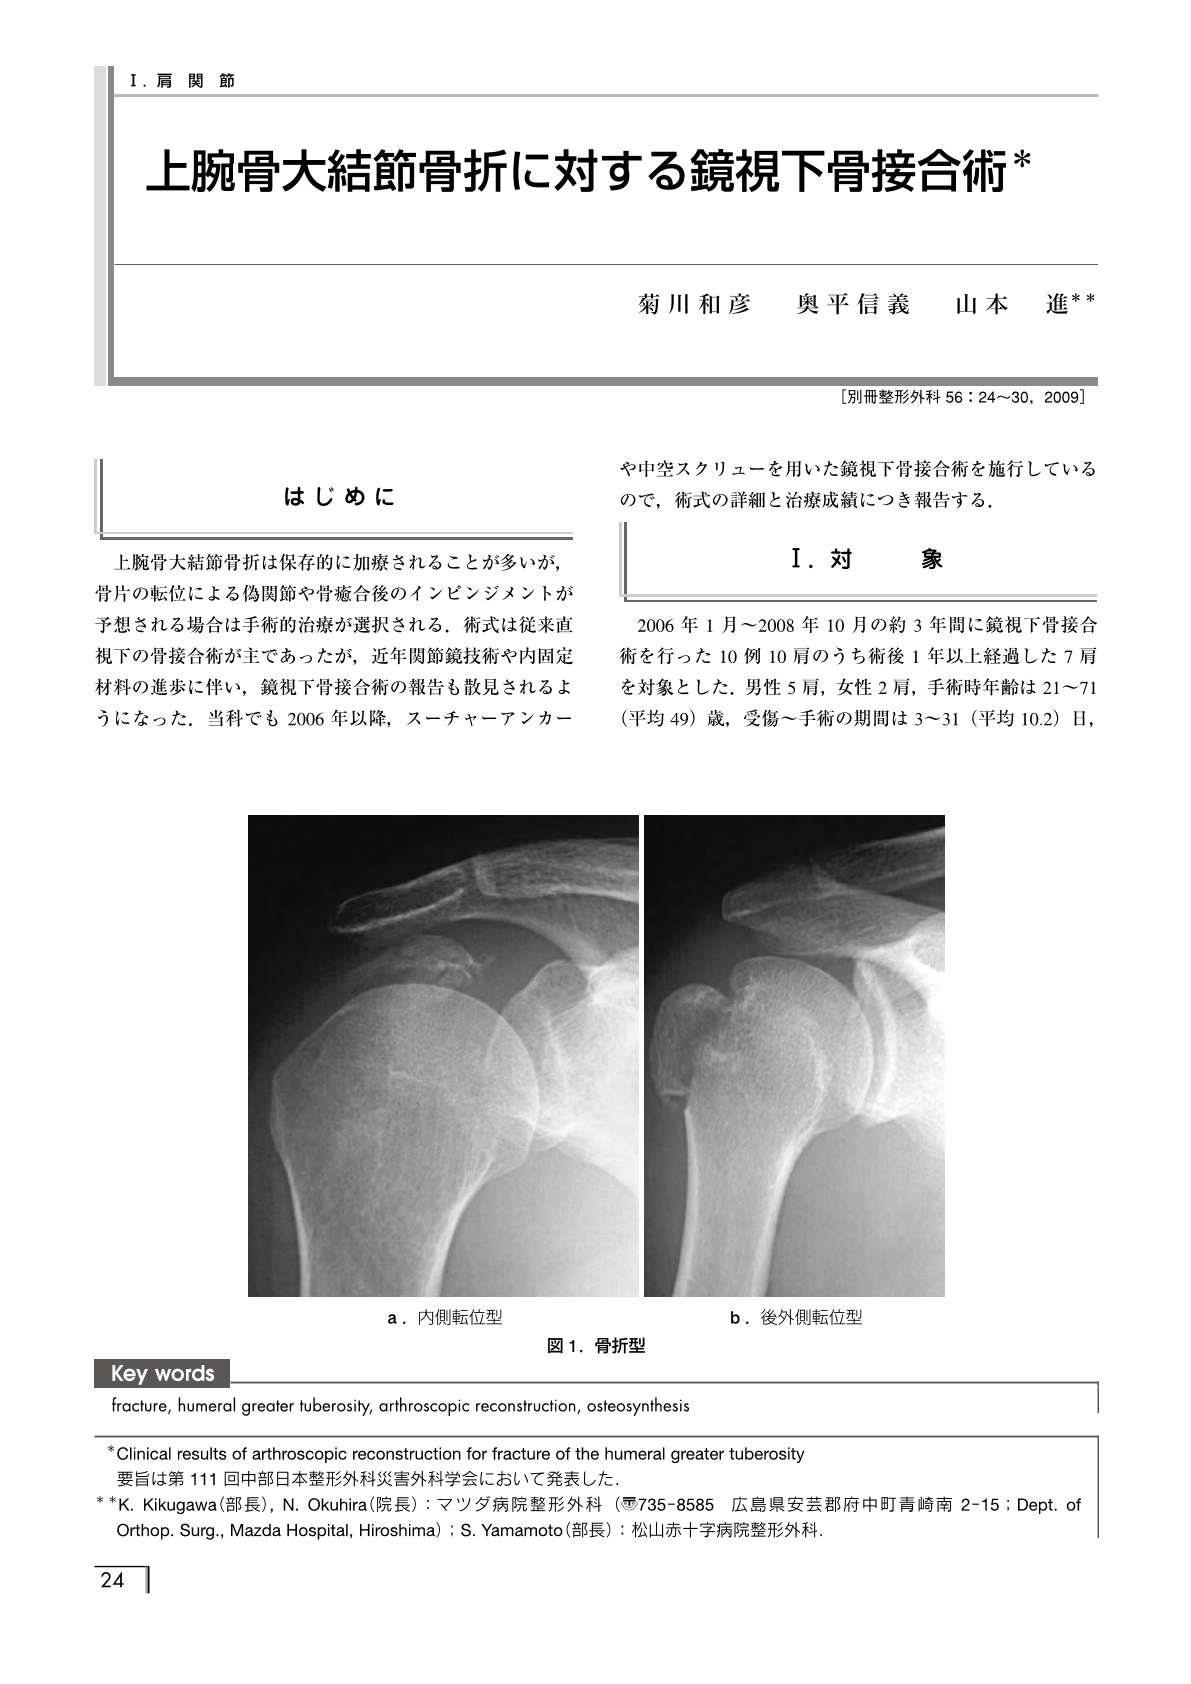

肩関節 上腕骨大結節骨折に対する鏡視下骨接合術 別冊整形外科 1巻56号 医書 Jp

上腕骨大結節骨折に対する8の字鋼線締結法後に 裂離型大結節骨折を生じた1例 臨床整形外科 47巻9号 医書 Jp

上腕骨大結節骨折に対しbridging Suture法による鏡視下骨接合術を施行した1例 臨床雑誌整形外科 65巻13号 医書 Jp